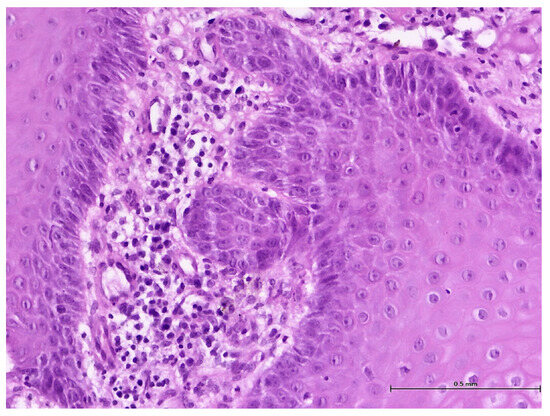

A Retrospective Histological Study on Palatal and Gingival Mucosa Changes during a Rapid Palatal Expansion Procedure

3. Results